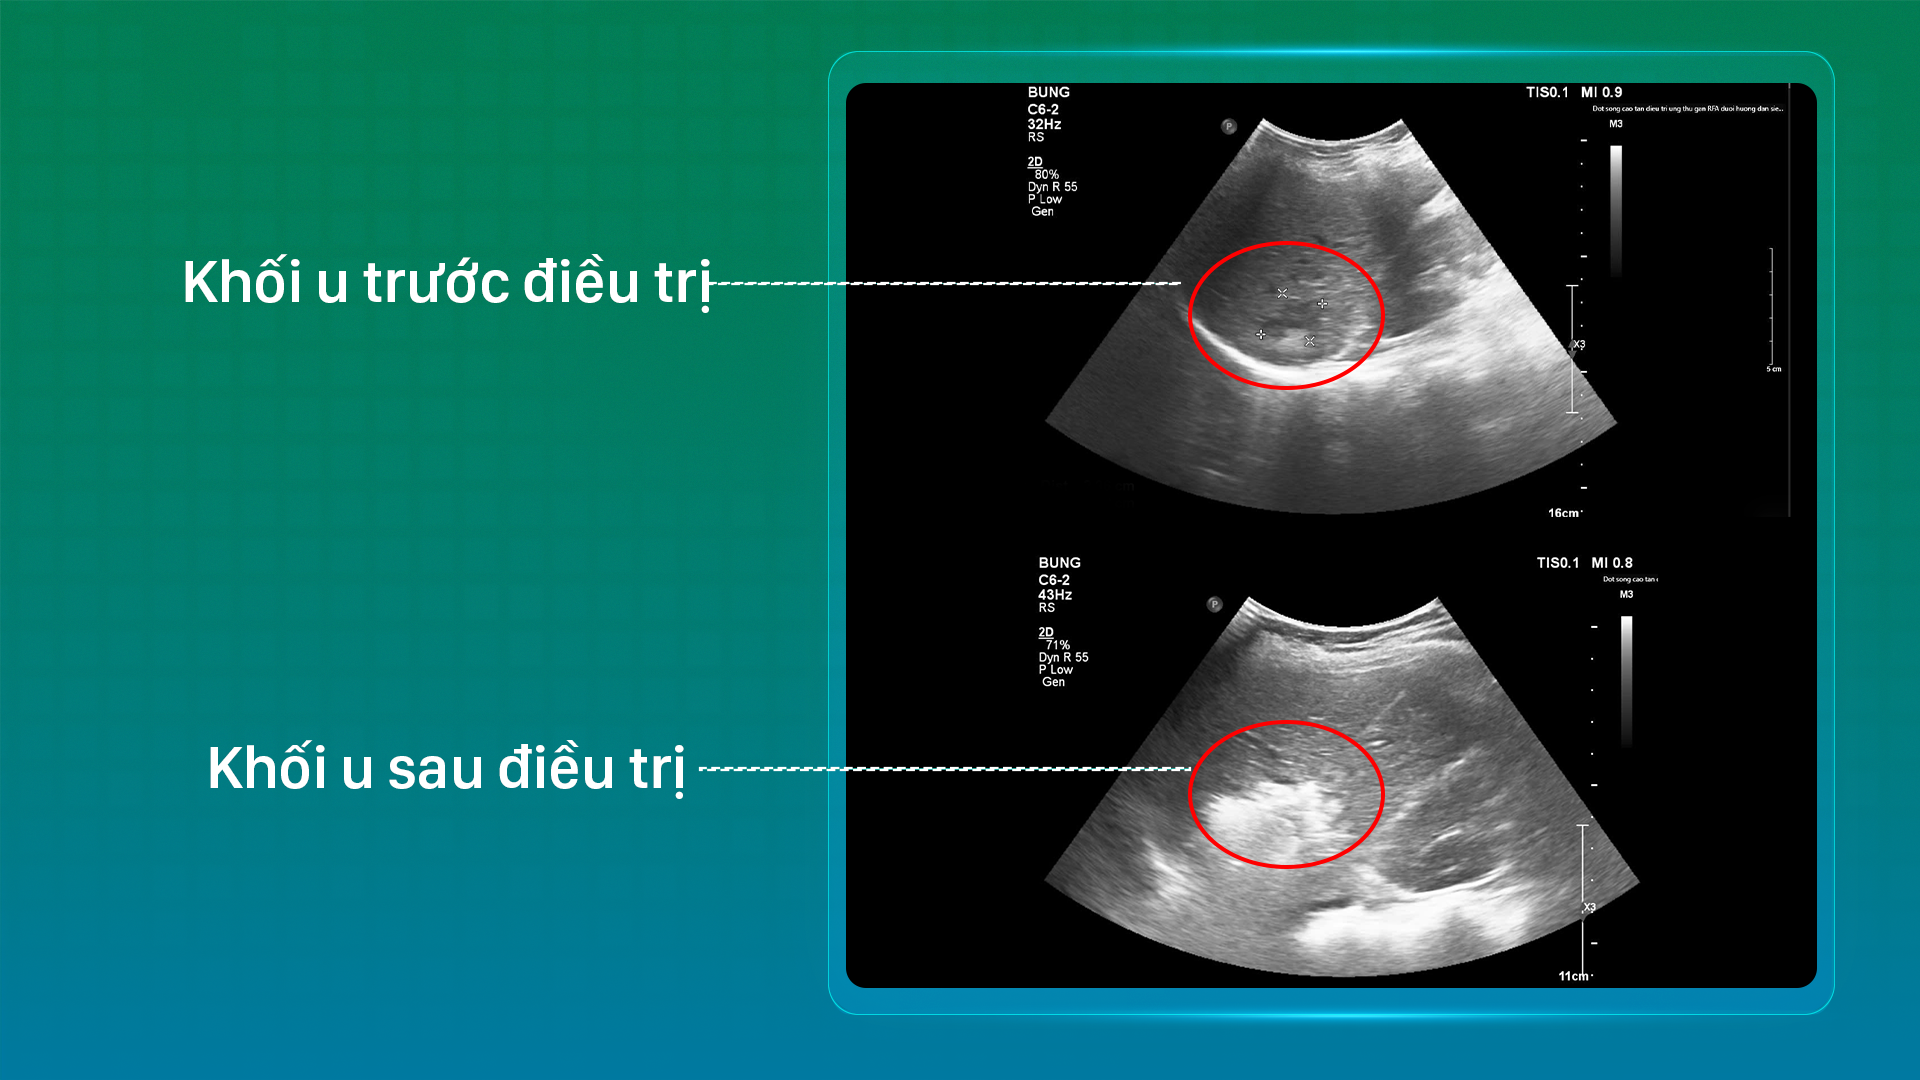

Khối u trước và sau điều trị của bệnh nhân

Chỉ sau 24 giờ, bệnh nhân có thể tự sinh hoạt bình thường, tinh thần phấn chấn và được xuất viện sớm trong sự ngỡ ngàng của người thân.